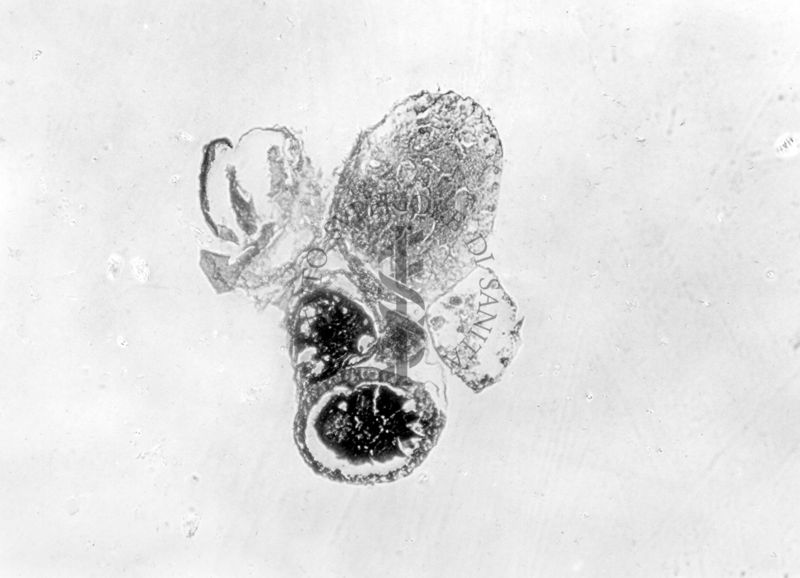

Sezione di un testicolo articolato ad un ovidutto, gonadi con epitelio esterno di sesso opposto ai prodotti sessuali, sezione di 2 gonadi di sesso opposto, immature e articolate a ovidutti

Gonadi con epitelio esterno di sesso opposto ai prodotti sessuali